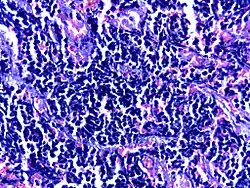

![]() |

Small cell carcinoma of lung | Micograph of small Cell Carcinoma Lung. The tumor appears blue because the malignant epithelial cells are small with scanty cytoplasm, nuclei shows finely granulated chromatin. Cells are seen in clusters. There is nuclear overlapping with moulding and crushing. | Category: Histopathology of small cell lung cancer | Small cell lung cancer |